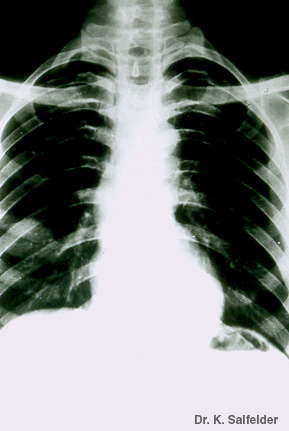

Abb. 12,3: Kryptokokkose

Der einzelne Herd im rechten Lungenunterlappen wurde als Karzinom reseziert. Erst die Histologie ergab eine Pilzinfektion. Resektionspraeparat siehe Abb. 12, 4